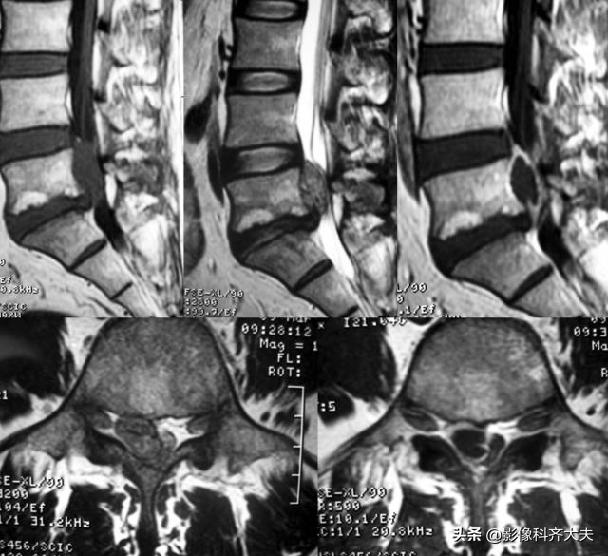

MRI:腰4、5间盘变性、突出,硬膜囊受压

MRI:腰椎间盘突出

MRI:腰 5-骶1间盘脱出

MRI:腰椎间盘脱出